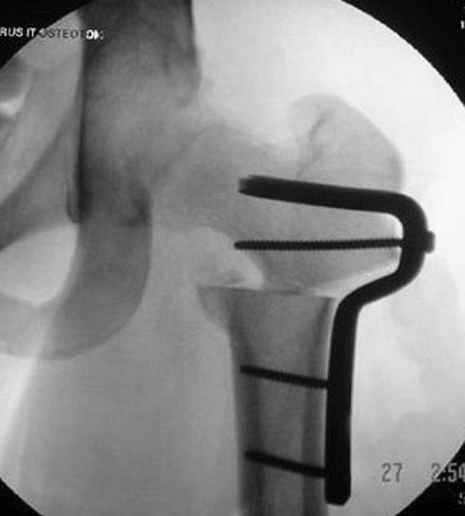

Несколько снимков из моей коллекции, чтобы разьяснить, почему мы до сих пор делаем различные варианты остеотомии.

N3 рисунок окончательный снимок, после операции моя рентгенограмма должен выглядеть примерно как эта картина. На N4 снимке клин перед удалением; N5 послеоперации 3 нед.; N6 окончательная рентгенограмма.

варус при проксимальном отделе 95 градусной пластиной.